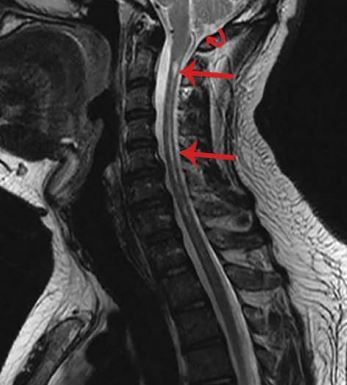

chiari畸形伴脊髓空洞症.中年女性,行走不稳,眼震,眩晕 - 抖音

图片尺寸1280x1706